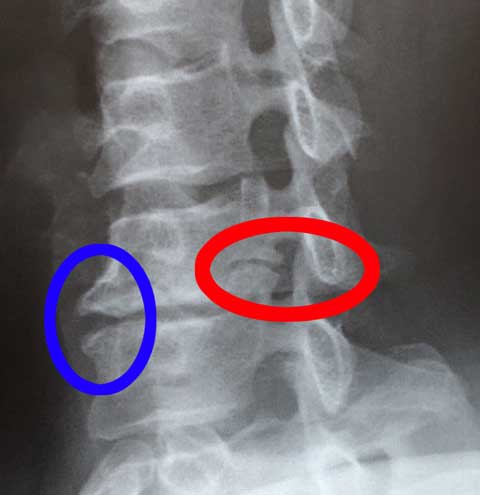

ややこしい病名は忘れましたが(笑)、第6頸椎に問題があって神経を圧迫しているとのこと。

赤丸の所ですが、上下と比較して明らかに楕円の部分が変形して細くなっています。

青丸の所もが尖っていて『なにか激しいスポーツしてましたか?』と聞かれてしまいました。「否、特にしていませんが・・・」と言ったところで「その昔、激しくスノボしてましたけど…」という前に話がぶった切られてしまいました(爆)

で、問題の穴の部分から神経が出ているんですが、通り道が狭くなっているために傷ついて痛みに繋がるんだそうで。。。